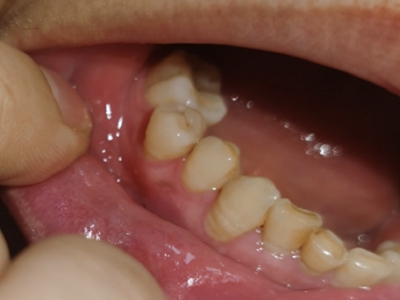

楔状缺损与年龄相关,即年龄越大,缺损越重,患者多有横刷牙习惯,患牙为多颗甚至全口,常以口角附近的牙齿(尖牙、前磨牙)为重。典型表现为牙颈部缺损,呈楔形,由两个夹面组成,口大底小,缺损处质地坚硬,表面光滑,边缘整齐,无染色,轻微泛黄常为牙齿本色,严重时可导致牙髓腔暴露甚至牙齿横向折断,根据缺损深浅不同,可伴有牙齿敏感甚至疼痛。

如果楔状缺损不深、症状不明显,可以不处理,有过敏症状可进行脱敏治疗。楔状缺损较深者可行充填修复。缺损达到牙髓腔,导致牙髓感染、根尖周病或牙齿横折者,可进行根管治疗、拔除患牙,再进行修复。平时要采取正确的刷牙手法,例如巴氏刷牙法,避免咬硬物。必要时通过正畸、修复等方法调整咬合关系。